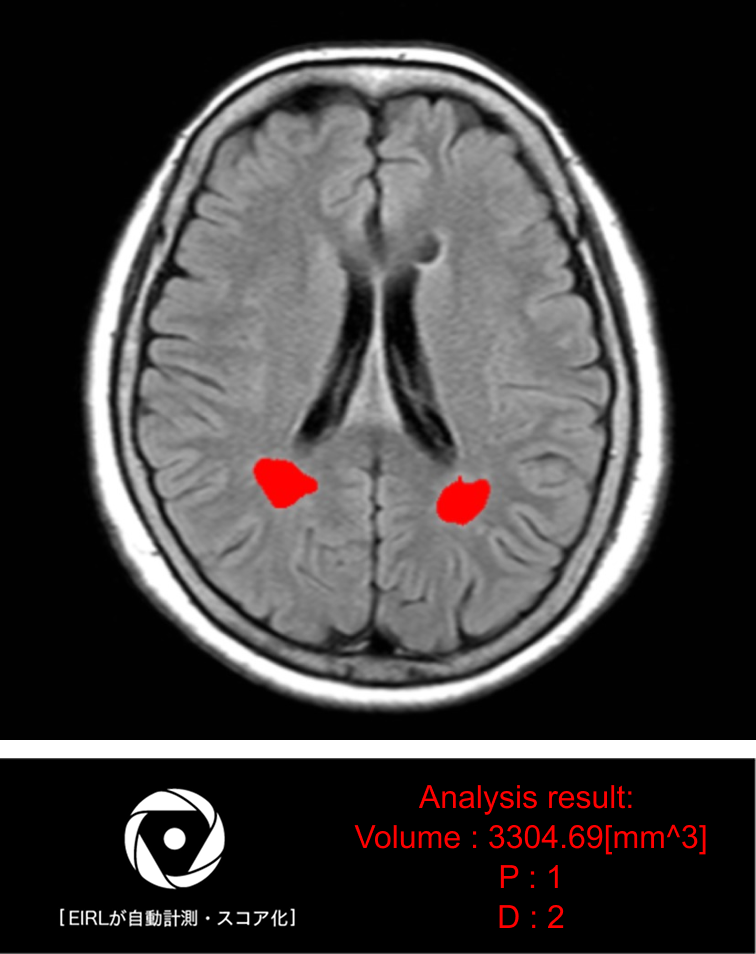

- 白質高信号領域の体積を測定した結果を元にしたP/Dスコア*の出力(エルピクセルが独自にスコアリング)

* P/Dスコアとは

白質高信号領域の体積を測定した結果を元に、エルピクセルが独自にスコアリングしたものです。

Pスコア:脳室周辺白質高信号領域(PVH)

Dスコア:深部皮質下白質高信号領域(DSWMH)

解析事例

体積とスコアは、サマリとして最後のスライスに出力されます